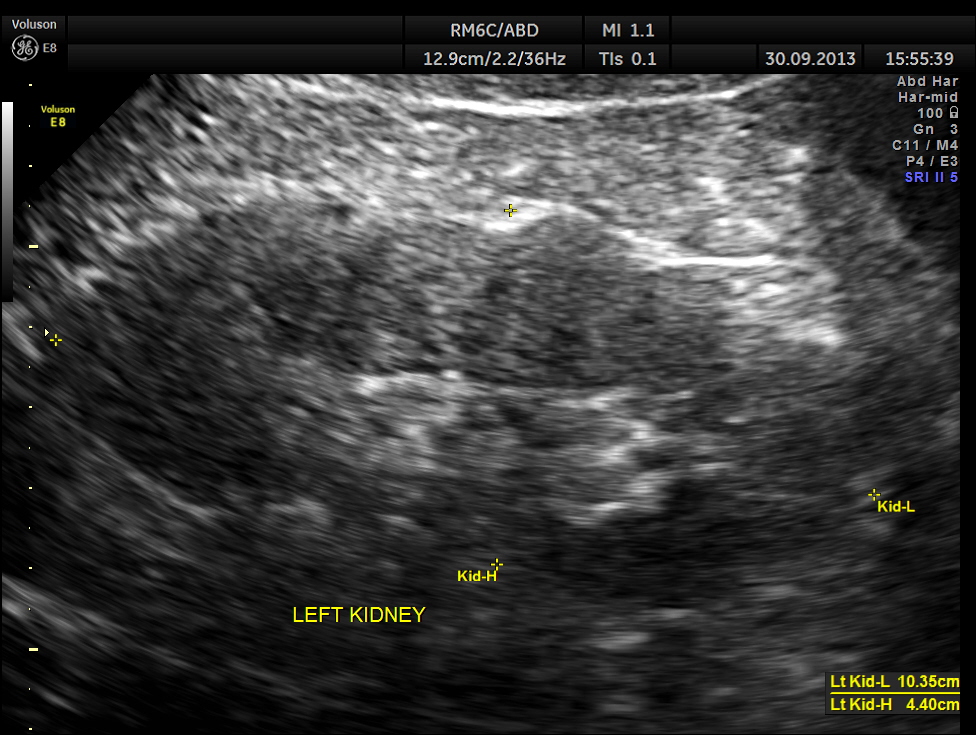

His upper abdominal scan was normal . His left kidney was normal.